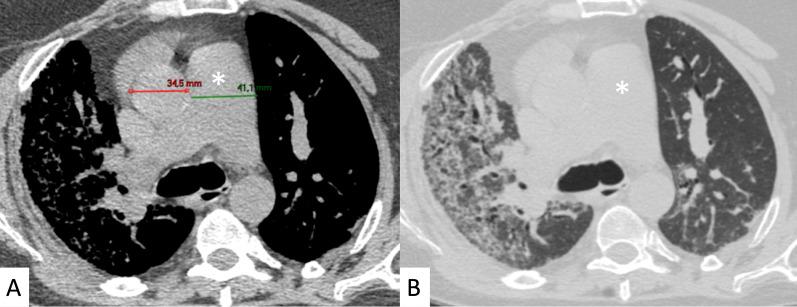

Connective tissue diseases (CTDs) include a spectrum of disorders that affect the connective tissue of the human body; they include autoimmune disorders characterized by immune-mediated chronic inflammation and the development of fibrosis. Lung involvement can be misdiagnosed, since pulmonary alterations preceded osteo-articular manifestations only in 20% of cases and they have no clear clinical findings in the early phases. All pulmonary structures may be interested: pulmonary interstitium, airways, pleura and respiratory muscles. Among these autoimmune disorders, rheumatoid arthritis (RA) is characterized by usual interstitial pneumonia (UIP), pulmonary nodules and airway disease with air-trapping, whereas non-specific interstitial pneumonia (NSIP), pulmonary hypertension and esophageal dilatation are frequently revealed in systemic sclerosis (SSc). NSIP and organizing pneumonia (OP) may be found in patients having polymyositis (PM) and dermatomyositis (DM); in some cases, perilobular consolidations and reverse halo-sign areas may be observed. Systemic lupus erythematosus (SLE) is characterized by serositis, acute lupus pneumonitis and alveolar hemorrhage. In the Sjögren syndrome (SS), the most frequent pattern encountered on HRCT images is represented by NSIP; UIP and lymphocytic interstitial pneumonia (LIP) are reported with a lower frequency. Finally, fibrotic NSIP may be the interstitial disease observed in patients having mixed connective tissue diseases (MCTD). This pictorial review therefore aims to provide clinical features and imaging findings associated with autoimmune CTDs, in order to help radiologists, pneumologists and rheumatologists in their diagnoses and management.

结缔组织病(CTDs)包括一系列影响人体结缔组织的疾病;它们包括以免疫介导的慢性炎症和纤维化发展为特征的自身免疫性疾病。肺部受累可能会被误诊,因为肺部改变仅在20%的病例中先于骨关节炎表现出现,且在早期阶段没有明确的临床发现。所有肺部结构都可能受累:肺间质、气道、胸膜和呼吸肌。在这些自身免疫性疾病中,类风湿关节炎(RA)的特征是普通型间质性肺炎(UIP)、肺结节和伴有空气潴留的气道疾病,而系统性硬化症(SSc)常表现为非特异性间质性肺炎(NSIP)、肺动脉高压和食管扩张。NSIP和机化性肺炎(OP)可见于多发性肌炎(PM)和皮肌炎(DM)患者;在某些情况下,可观察到小叶周围实变和反晕征区域。系统性红斑狼疮(SLE)的特征是浆膜炎、急性狼疮性肺炎和肺泡出血。在干燥综合征(SS)中,HRCT图像上最常见的表现是NSIP;UIP和淋巴细胞间质性肺炎(LIP)的报道频率较低。最后,纤维化NSIP可能是混合性结缔组织病(MCTD)患者中观察到的间质性疾病。因此,本图像综述旨在提供与自身免疫性CTDs相关的临床特征和影像学表现,以帮助放射科医生、呼吸科医生和风湿病科医生进行诊断和管理。